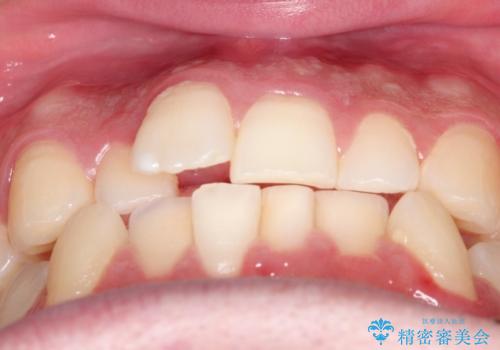

初診時の歯並びの状態としては、上下ともに前歯部の中等度以上のがたつき(叢生)があり、右の前歯が1本飛び出した状態でした。

抜歯は行わず上下顎ともに、主に歯列弓の拡大とディスキング(歯と歯の間に隙間を作る処置)を行い叢生を改善しました。